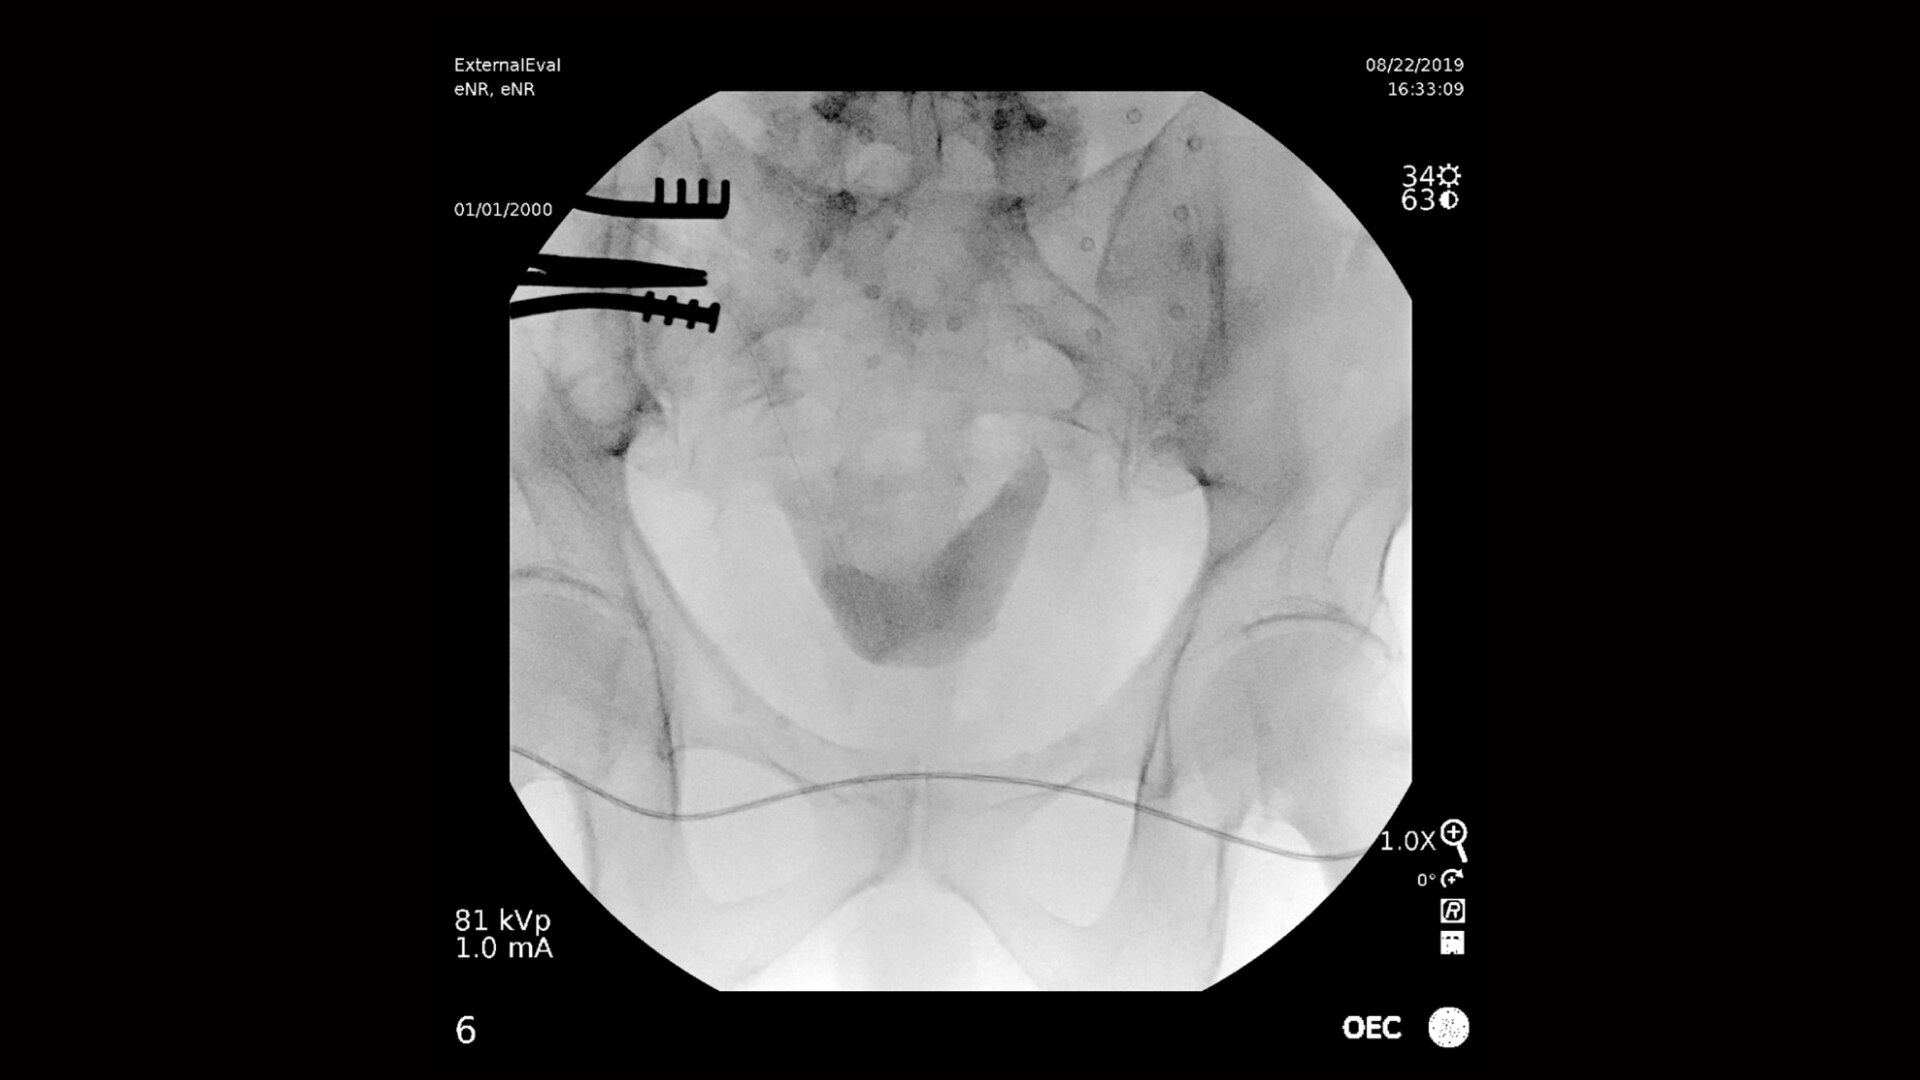

OEC mobile C-arms deliver incredible image quality and large field of view for comprehensive visualization of the urinary anatomy. The streamlined design provides more access and flexibility for an optimal urology suite set up.

Clearly visualize the entire urinary tract from the kidneys to the bladder during urology procedures. OEC C arms deliver amazing image quality allowing interventionalists to easily identify small details of urinary anatomy, such as urological cavities. A clear display with large field of view provides comprehensive visualization without need for repositioning an OEC C-arm, enabling an effortless workflow

Urology imaging you need

Complex urology procedures require powerful imaging systems.

OEC premium C-arms perform in a variety of procedures such as:

• Abdominal radiography

• Brachytherapy

• Cystoscopy

• Intravenous pyelography

• Retrograde pyelogram

• Percutaneous nephrolithotomy

• Transurethral resection of the prostate

• Urodynamics